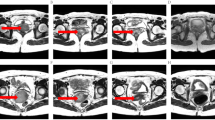

This retrospective study included 115 patients with surgically proven cervical cancer who underwent preoperative pelvic 3T-MRI, and MRTA was performed on T2-weighted images (T2), apparent diffusion coefficient (ADC) maps, and contrast-enhanced T1-weighted images (CE-T1). Filtration histogram-based texture analysis was used to generate six first-order statistical parameters [mean intensity, standard deviation (SD), mean of positive pixels (MPP), entropy, skewness, and kurtosis] at five spatial scaling factors (SSFs, 2–6 mm) as well as from unfiltered images. Cox proportional hazard models and time-dependent receiver operating characteristic analyses were used to evaluate the associations between parameters and recurrence-free survival (RFS).